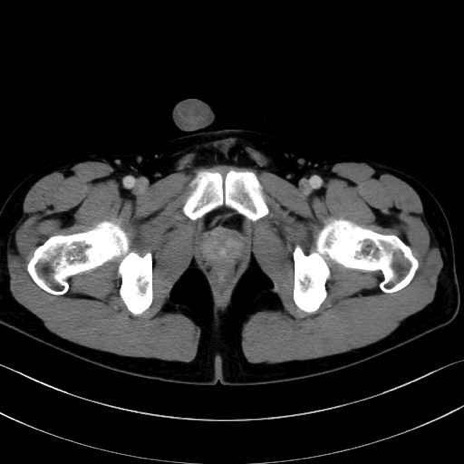

梨状筋(piriformis muscle) のCT画像の解剖

外閉鎖筋 (Obturator externus)

大腿方形筋 (Quadratus femoris)

恥骨筋 (Pectineus)